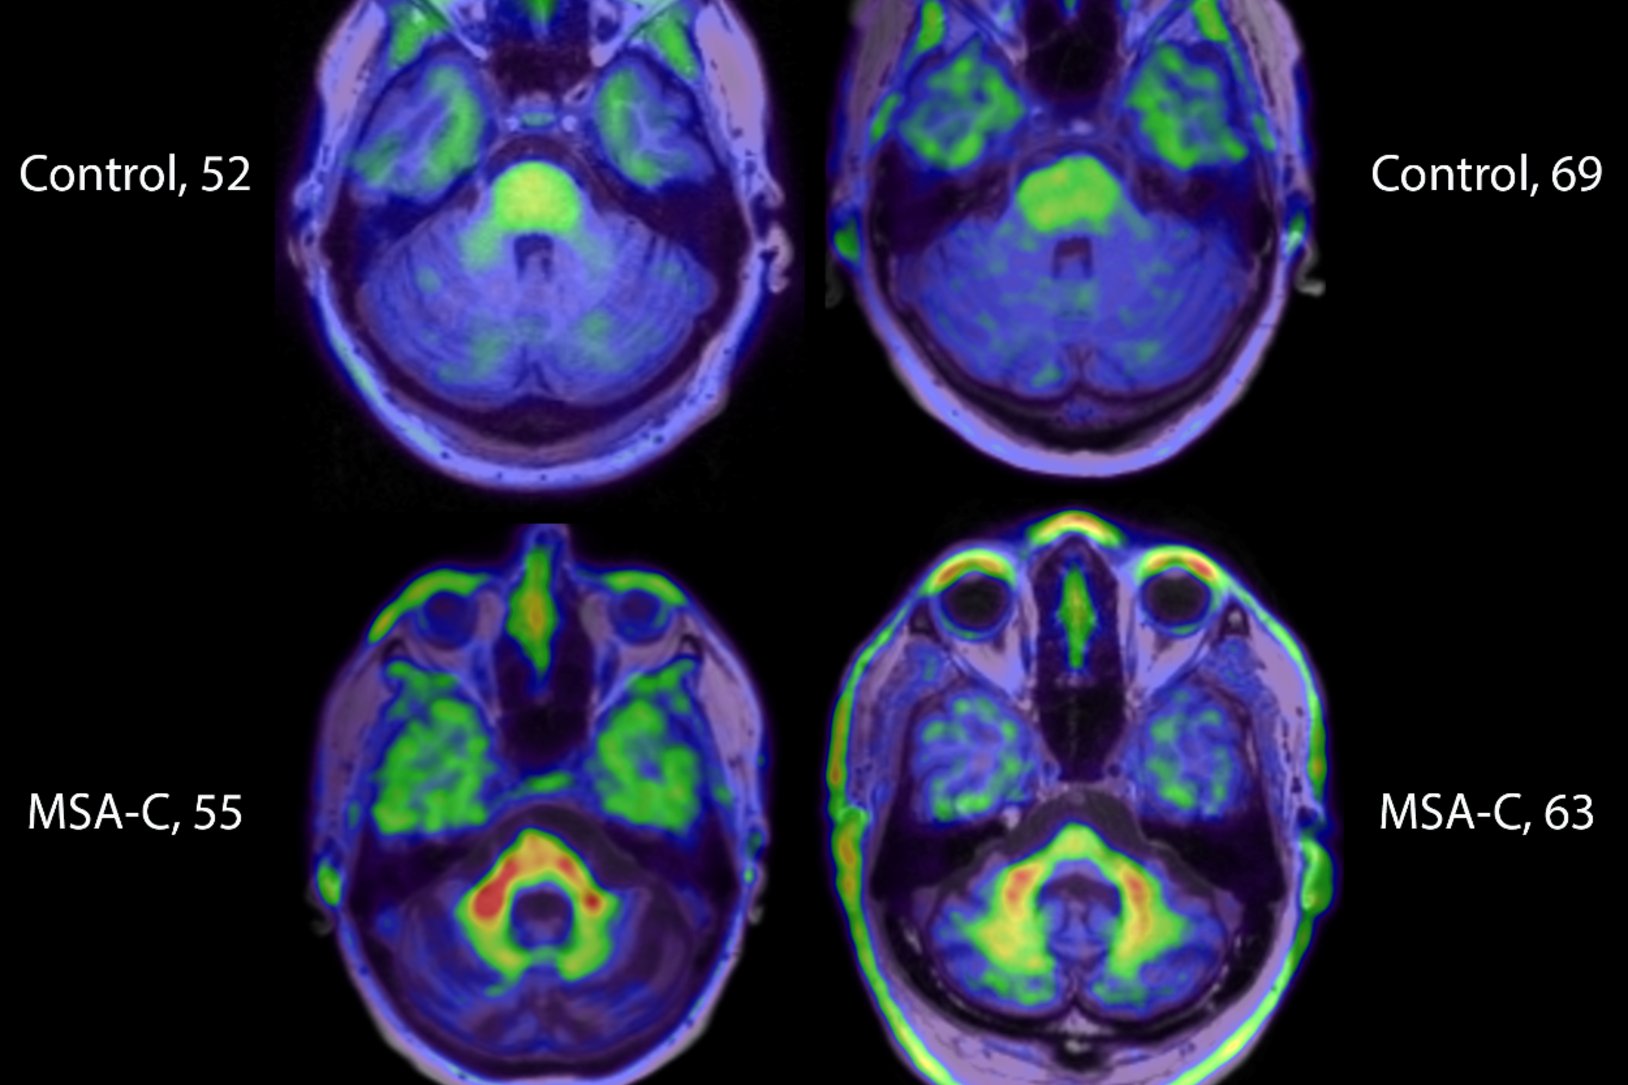

Michaeljfox Org On Twitter Breaking News Late Last Week A Research Team Funded By The Michael J Fox Foundation Announced Important Progress Around Imaging The Protein Alpha Synuclein A Top Research Priority Because